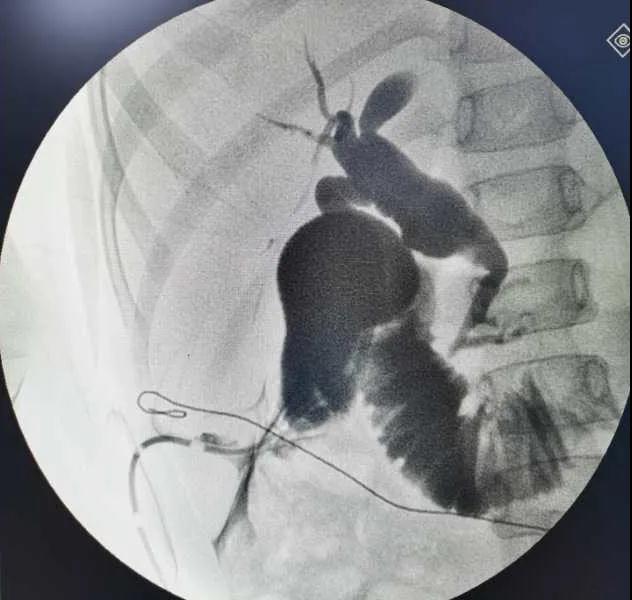

5月7日,西安國(guó)際醫(yī)學(xué)中心醫(yī)院小兒外科郭正團(tuán)教授團(tuán)隊(duì)成功為1名膽總管囊腫患兒進(jìn)行了腹腔鏡膽管造影 腹腔鏡膽總管囊腫切除 腹腔鏡肝管空腸吻合術(shù)。目前,患兒恢復(fù)良好,已正常進(jìn)食。

入院后,謝崇醫(yī)生積極為患兒完善術(shù)前準(zhǔn)備,MRCP(核磁共振膽道水成像)顯示該患兒為膽總管囊腫Ic型,有明顯的胰膽合流異常。面對(duì)復(fù)雜的病情,小兒外科郭正團(tuán)主任立即組織團(tuán)隊(duì)進(jìn)行術(shù)前討論,制定了完善的手術(shù)方案及應(yīng)急措施。

5月7日,一切準(zhǔn)備就緒,郭正團(tuán)主任主刀,帶領(lǐng)小兒外科團(tuán)隊(duì)進(jìn)行腹腔鏡膽管造影 腹腔鏡膽總管囊腫切除 腹腔鏡肝管空腸吻合術(shù)。術(shù)中,患兒膽總管與周圍肝動(dòng)脈及門靜脈粘連嚴(yán)重,給手術(shù)增加了難度。郭正團(tuán)主任沉著冷靜,操作嫻熟,完整剝離了膽總管囊腫及遠(yuǎn)端胰腺段膽管,肝總管與空腸完成了Roux-en-Y吻合,手術(shù)進(jìn)行順利。術(shù)后第2天,玲玲就可以下床活動(dòng);第6天,已正常飲食。